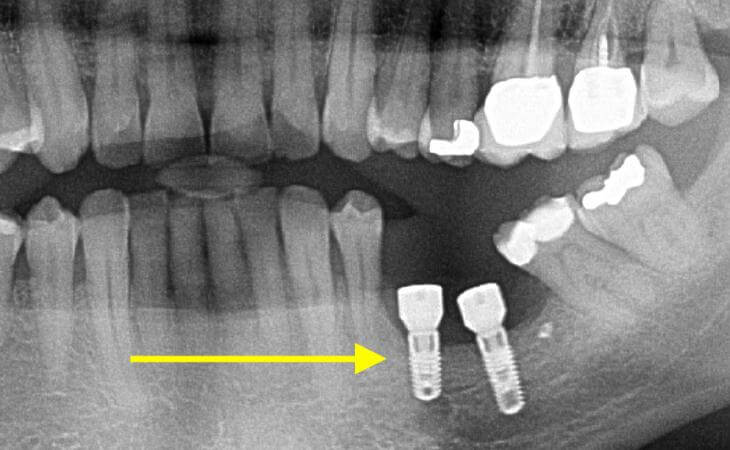

Patient had a 3 unit bridge that was decayed. A CT scan was taken to evaluate the surrounding bone. Patient underwent extraction and Bone Grafting to regenerate and build the necessary bone for implant placement. Implant was placed. Final x-ray showing 3 implants placed to replace the bridge.